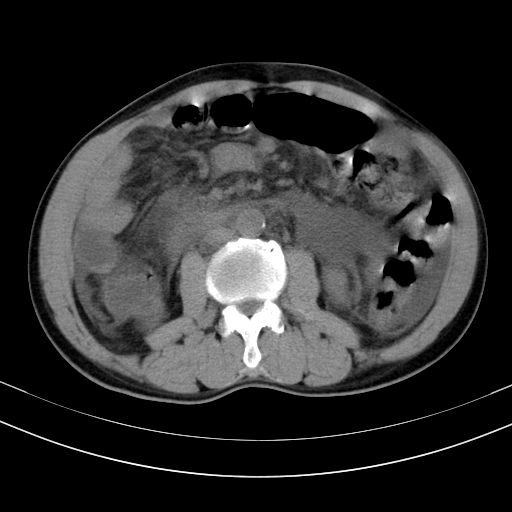

以下是引用随光逐影在2010-2-28 10:23:00的发言:[br]1)考虑肝癌;建议行ct增强扫描检查。2)肝硬化,脾大,腹水。3)慢性胆囊炎。

以下是引用dyqct在2010-2-28 16:44:00的发言:[br][quote]以下是引用随光逐影在2010-2-28 10:23:00的发言:[br]1)考虑肝癌;建议行ct增强扫描检查。2)肝硬化,脾大,腹水。3)慢性胆囊炎。